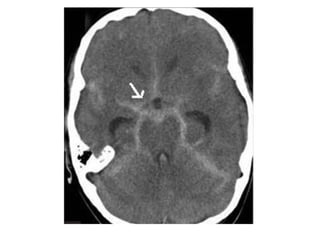

Patient with acute vision loss in the right half of the visual field ,

CT shows an infarction in the contralateral visual cortex , i.e

left occipital lobe

PCA infarction , notice the loss of gray / white matter differentiation in

the region of the left occipital lobe